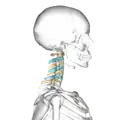

شكل الفقرات العنقية موضح بالأصفر و الأزرق.

صورة جانبية للفقرات العنقية موضح بالأزرق و الأصفر.